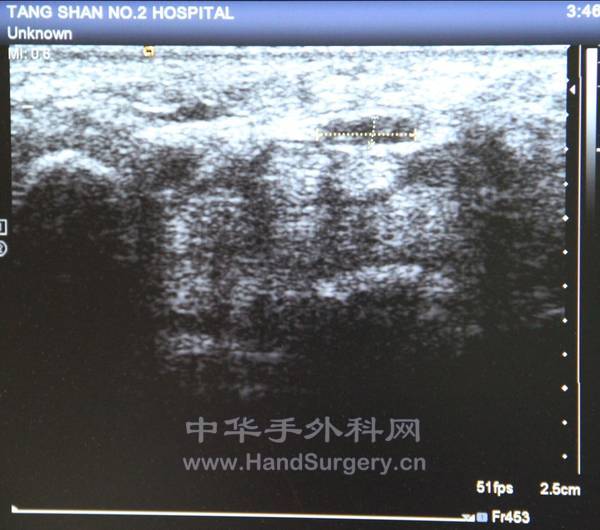

带标记的,黑色的是正中神经

下边白色的是屈指肌腱

正中神经受到卡压,左右径宽,前后径窄

横切面呈扁椭圆状,甚至片状

正常应该呈椭圆型